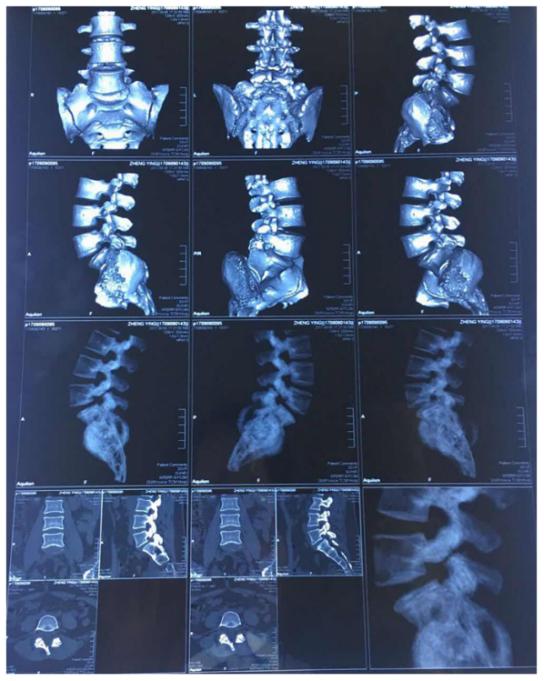

影像资料

从影像资料可以看到腰5峡部裂造成腰5骶1滑脱,滑脱有Ⅰ度。患者双侧峡部裂,也就是是由于腰部突然受力等原因导致左右两侧的椎弓峡部都断裂,但是患者只有三十多岁,比较年轻,肌肉力量比较强,避免断裂后继续向前滑移。

目前,患者峡部断裂的地方已经出现假关节,说明断裂时间已经比较长,至少六个月;患者腰5和骶1锥体关节面已经斜行向下,如果后方的力量不足,滑脱会持续向下进行。腰椎的反复滑脱会影响导致腰椎小关节增生、椎间盘损伤和局部韧带的松弛。所以,临床上建议峡部裂造成的滑脱是应该早做手术、只有手术才能防止进一步滑脱。

临床上,患者在做影像检查的时候会在站位和坐位出现明显的不同。比如这位患者核磁和CT是躺下来拍的,侧位平片是站立时拍的或卧位(但是时间较短)明显可以看到侧位平片显示的滑脱更严重。那么,腰椎滑脱该怎么判断已经发展到几度了呢?一般来说,患者在出现症状以后到医院做检查,此时如果做站立位腰椎侧位平片,可以明确滑脱的程度。